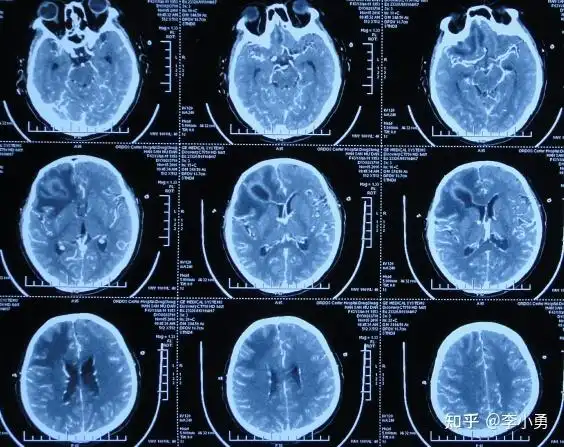

一例脑梗死患者的ct演变及治疗过程

3月18日复查头颅ct

脑ct图片诊断